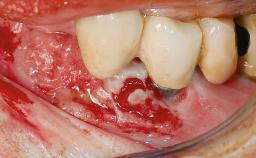

Peri-implantitis Modified by Submucosal Excess of Cement: Regenerative Peri-implantitis Therapy and Six-year Follow-up

A 30-year-old female patient was referred to the Department of Periodontology of the University of Bern, Switzerland, by a dentist in private practice. Tooth 45 had been congenitally missing and had been replaced with a titanium implant three years prior to the first visit at the Department of Periodontology. The tissue level implant had a diameter of 4.1 mm, a length of 12 mm, and a sandblasted and acid-etched (SLA) surface (Straumann® Dental Implant System; Institut Straumann AG, Basel, Switzerland). The metal-ceramic crown on implant 45 had been cemented permanently. Implant 45 had been diagnosed with peri-implantitis by the referring dentist in the course of regular supportive care.